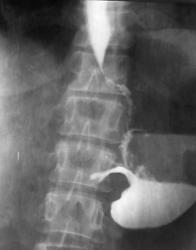

Окончательно можно сказать одно что идёт симметричное сужение просвета антрального отдела, рельеф слизистой не прослеживается, стенки регидны.

1- синдром сужения просвета пищеварительной трубки, а именно стойкое симметричное сужение, абсолютно на всех снимках и даже после приёма "шипучки" и не говоря уже про введения атропина

2- синдром изменения слизистой, в месте где идёт сужение мы рельефа слизистой не наблюдаем, ну а первое что меня насторожило это конвергенция складок в проекции синуса желудка

3- это не мало важный признак, изменение эластичности и перестальтики полого органа, видно на всех снимках симптом регидности стенок антрального отдела;

Аналогично и у автора представленных снимочков, антральный отдел сужен с переходом на превратник, а так же процесс идет по малой кривизне, вот только не понятно с кардиальным отделом, он кажется тоже деформирован. По степени же стенозаснимки надо обязательно сделать через 12 и 24 часа что бы решить есть или нет декомпенсированный стеноз. В этом слачае видно что в желудке много слизи, смею предположить о декомпенсированном стенозе.

Уважаемые коллеги! Спасибо за внимание к представленным мною снимкам.У пациента инфильтративный рак с полным стенозом антрального отдела и поражением тела желудка а также с переходом на кардиальный отдел.Валентин Львович Вы правы поповоду интермедиарного слоя - это остатки непереваренной пищи которые взболтались после исследования в горизонтальном положении а эвакуации не было вообще

Уважаемый v1tal! Спасибо за ваши снимки и комментарии.Вы полностью правы стеноз полный а кардиальный отдел тоже поражен